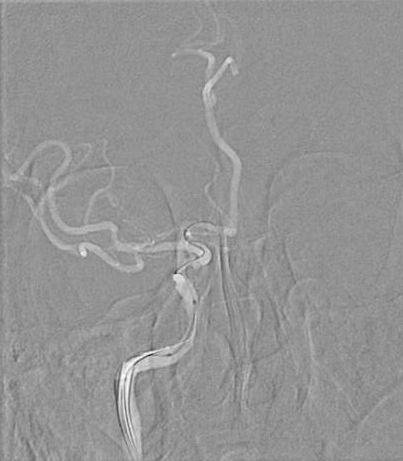

治疗过程

将 6F 导引导管送至 C3 段。

导丝怎么扩【载药时代 球扩天下】NOVA DES®颅内药物洗脱支架在颈内动脉颅内段重度狭窄中的应用体会二例!_https://www.jmylbn.com_新闻资讯_第24张

导引导管到位,导丝通过病变

通过微导丝携带球囊至狭窄段。

导丝怎么扩【载药时代 球扩天下】NOVA DES®颅内药物洗脱支架在颈内动脉颅内段重度狭窄中的应用体会二例!_https://www.jmylbn.com_新闻资讯_第25张

球囊通过病变

球囊到位后准确定位后缓慢扩张球囊。

导丝怎么扩【载药时代 球扩天下】NOVA DES®颅内药物洗脱支架在颈内动脉颅内段重度狭窄中的应用体会二例!_https://www.jmylbn.com_新闻资讯_第26张

球囊扩张过程

扩张后撤出球囊造影,见狭窄有所改善。

导丝怎么扩【载药时代 球扩天下】NOVA DES®颅内药物洗脱支架在颈内动脉颅内段重度狭窄中的应用体会二例!_https://www.jmylbn.com_新闻资讯_第27张

扩张后造影

通过导丝携带球扩支架到达病变位置。